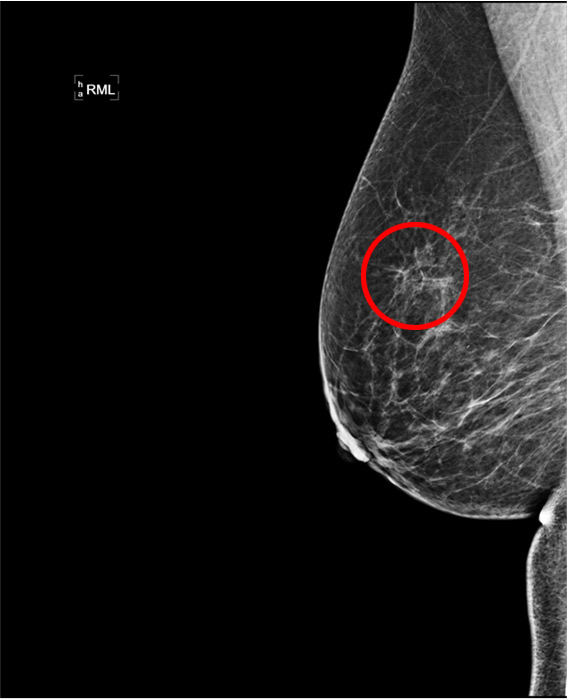

A: Kvinde på 60 år med følbar knude i højre bryst henvises til en mammaklinik. Mammografi viser et uregelmæssigt område (rød cirkel) i højre bryst.